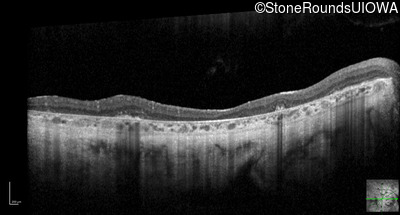

Optical Coherence Tomography - Right - 20/200 +2

Exemplar / OCT Stack